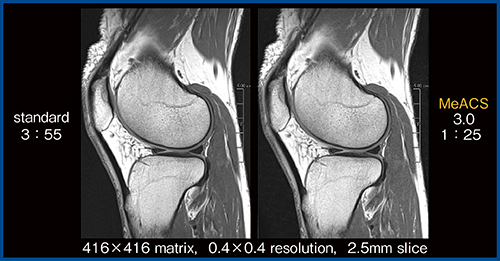

図6は膝の2D FSE画像で,0.4mm resolution,スライス厚2.5mmと非常に高分解能であるが,MeACSではSNRが低下することなく,コントラストを維持した画像が描出できている。

図6 膝の高分解能画像におけるMeACSの有用性(W.I.P.)